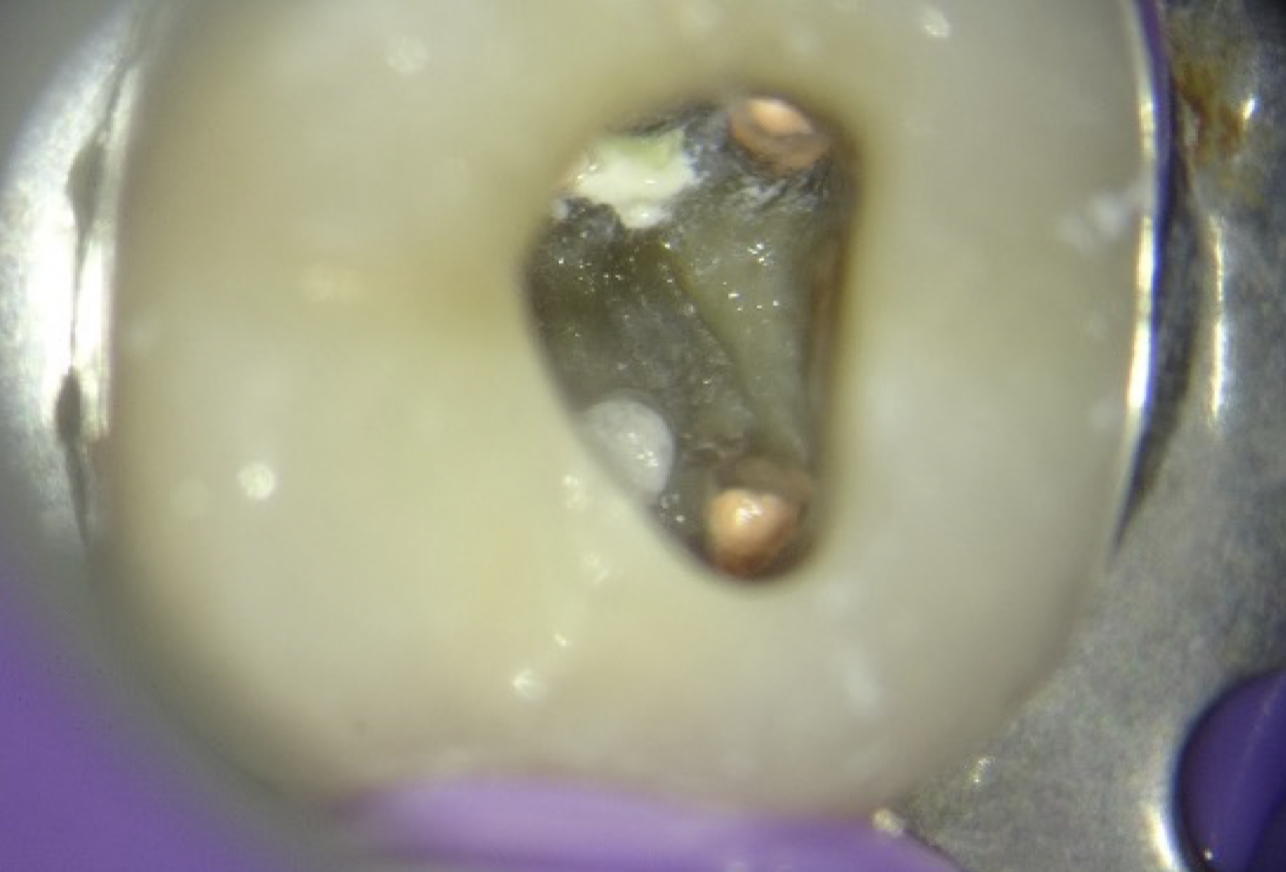

Fig. 5

Clinical picture showing pulpal floor perforation repaired with MTA.

Once haemostasis was achieved, attention was directed toward sealing the perforation. Mineral trioxide aggregate (MTA; Produits Dentaires, Switzerland) was mixed to a putty-like consistency and delivered to the defect using the MAP system (Fig. 5). This system facilitated precise placement within the confined furcation area (Video 2). The material was placed incrementally under magnification and gently compacted with micro-pluggers to ensure optimal adaptation to the surrounding dentinal walls while avoiding extrusion. Careful inspection confirmed complete sealing of the defect.

A moist microbrush was placed over the MTA to promote adequate setting (Video 2). After initial setting, the access cavity was temporarily sealed. At the subsequent visit, the integrity and stability of the MTA repair were confirmed clinically, demonstrating a well-adapted seal at the perforation site (Fig. 6).